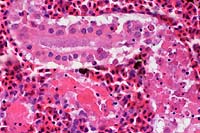

100x

obj

- Case 8-3. Kidney. One or more refractile protozoa

are found within many RBCs of congested interstitial capillaries.

There is fibrillar to amorphous proteinaceous material within

a collecting duct.

40x

- Case 8-3 . Kidney. The glomerulus contains increased

numbers of mesangial cells which compress glomerular capillaries.

Adjacent tubules are filled with eosinophilic material forming

hyaline casts.

Movat

Stain, 4x obj

- Case 8-3. Cardiac muscle. Myocardial muscle is partly

replaced by fibrous connective tissue (fibrosis).

4x

- Case 8-3. Colon. The lamina propria is markedly expanded

by diffuse hemorrhage which distorts and separates the mucosa

from the underlying tunica muscularis.